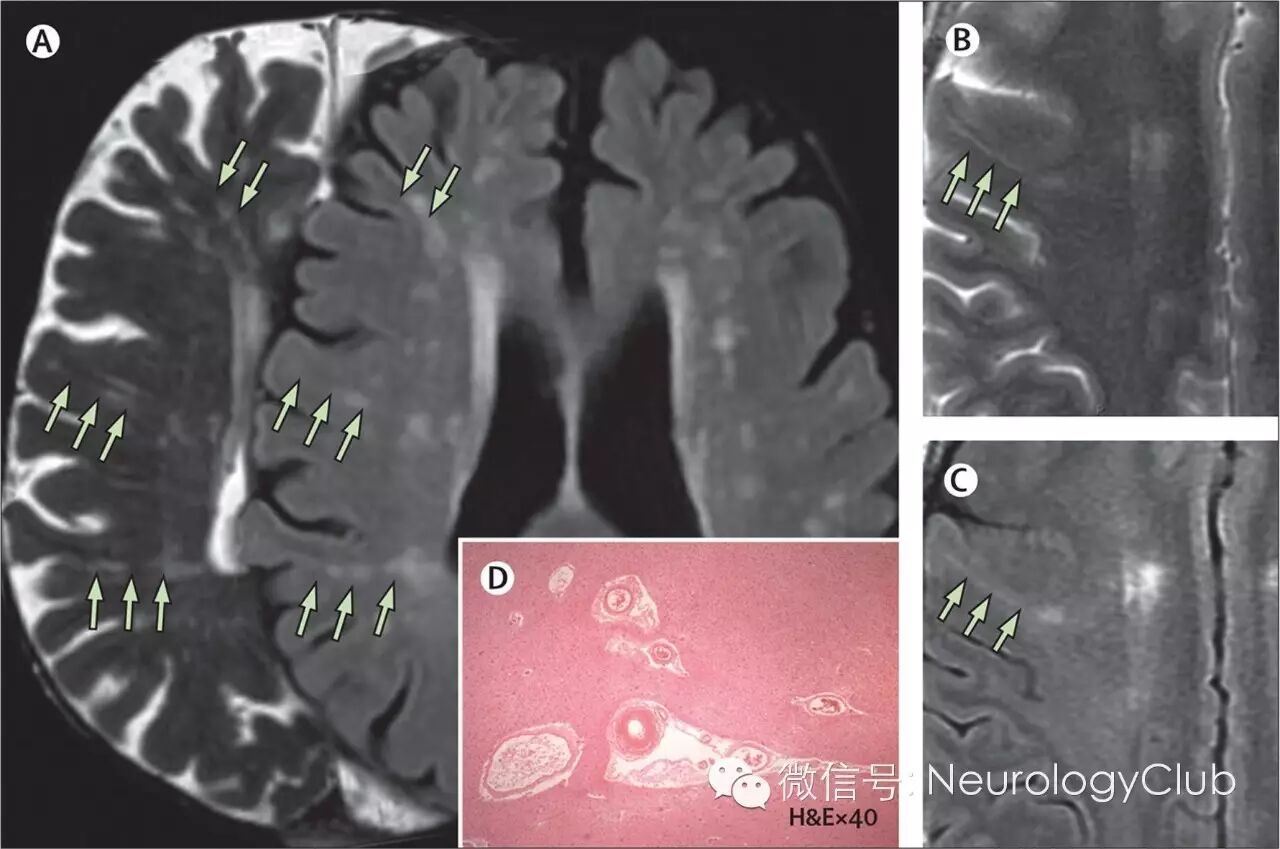

(A:72岁无症状患者,T2WI可见线状血管周围间隙,FLAIR可见血管周围间隙旁白质高信号;B:49岁男性,T2WI可见左侧内囊急性小梗死[未放图]和从脑室旁延伸至皮质下组织的血管周围间隙;C:相应的FLAIR上一处白质高信号位于血管周围间隙旁;D:组织学上的血管周围间隙,可见小穿支动脉旁脑实质回缩。多为老年脑的典型表现,常伴有CSVD